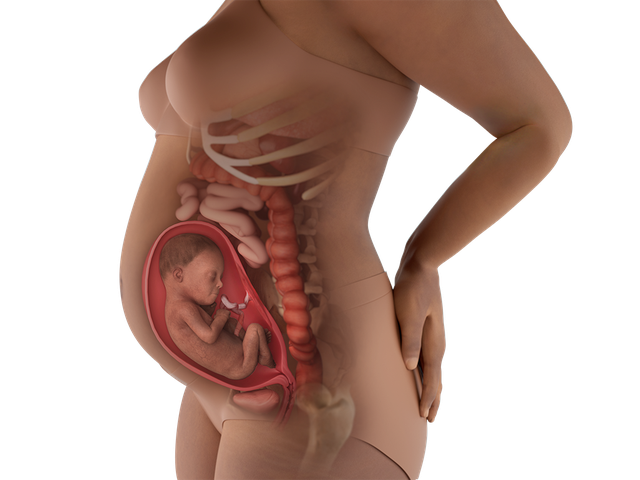

Trong tuần thai thứ 26, bé yêu đạt bước tiến quan trọng: mí mắt mở, phản xạ phát triển, và phổi tiếp tục hoàn thiện. Nhau thai cung cấp dinh dưỡng và oxy hiệu quả. Mẹ cảm thấy tràn đầy sức sống, nhưng có thể gặp khó ngủ hoặc sưng bàn chân do áp lực tử cung.

– Hormone ổn định: Progesterone và estrogen hỗ trợ thai kỳ, làm tử cung mở rộng, có thể gây khó ngủ, sưng bàn chân, hoặc táo bón.

– Bụng to rõ: Tử cung lớn hơn, khiến bụng nhô rõ, dễ nhận thấy khi đứng hoặc mặc quần áo ôm sát.

– Tăng cân: Mẹ có thể tăng 6-8 kg (tùy cơ địa), do thai nhi, nhau thai, và nước ối phát triển.

– Thay đổi khác: Mẹ tràn đầy sức sống, tiết dịch âm đạo (trắng đục, không mùi), tóc và móng mọc nhanh, da sáng mịn hoặc có đốm nám. Khó ngủ có thể xảy ra do tư thế nằm khó chịu hoặc lo lắng, và sưng bàn chân xuất hiện do tăng lưu lượng máu. Đau lưng hoặc đau dây chằng tròn vẫn có thể tiếp diễn.